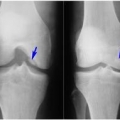

ДИАГНОСТИКА

Диагноз устанавливает врач после расспроса и осмотра больного. Обязательно проводятся лабораторные и инструментальные методы обследования: исследование крови, рентген, сцинтиграфия, МРТ, диагностическая артроскопия.

Медицинские процедуры, проводимые при заболевании болезнь кёнига: Клинический анализ крови, С-реактивный белок, Биохимический анализ крови, Рентген, Сцинтиграфия костей, Магнитно-резонансная томография, Артроскопия